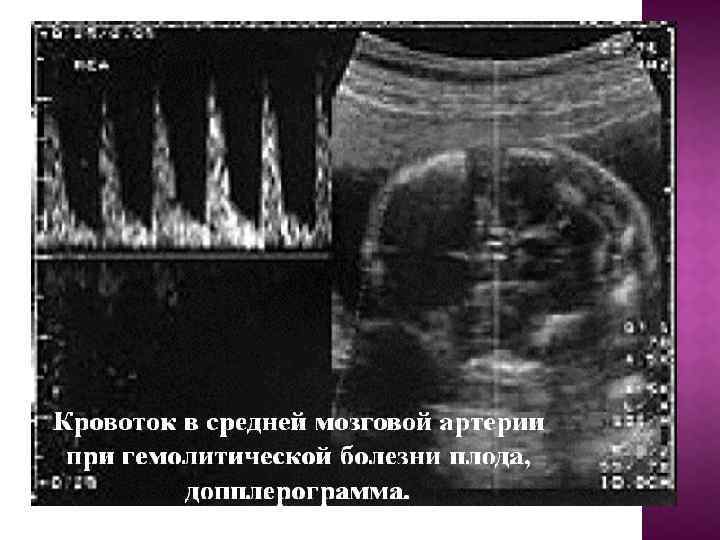

4) 20 -22, 24 -26, 30 -32, 34 -36 апталарда ұрық пен плацентаның УДЗ. Бұл кезде НГА – ның ісіну формасын (асцит, Будда қалпы), плацентаның қалыңдауы, гепатоспленомегалияны анықтауға болады. ҰГА- ның ультрадыбыстық маркеріне жатады: — ҰГА- ның ауыр формасында плацентаның > 50 мм ден аса қалыңдайды, плацентаның көлемінің ұлғаюы, құрылымның өзгерісі – эхограммада шар тәрізді бос аймақтардың пайда болуымен анықталады; — көпсулық (амниотикалық сұйықтықтың индексі > 24); көпсулық пен шеменнің қосарлануы жағымсыз болжамды айтады; — гидроперикард – ҰГА – ның ең ерте белгісінің бірі; — іштің көлемі бас пен кеуде клеткасының өлшемдерімен салыстырғанда ұлғаюы; — асциттің анықталуы ҰГА – ның айқын дәрежесі екенің куәландырады; — қарқынды экстрамедулярлы эитропоэздің күшеюінің салдарынан гепатомегалия дамиды; — тері асты шел майының ісінуі, әсіресе ұрықтың басынды айқын байқалады; — кардиомегалия; — кіндік венасының 10 мм –ден артық кеңеюі. НГА – ның ісінуі формасы жүктіліктің үзуінің көрсеткіштері болып табылады.